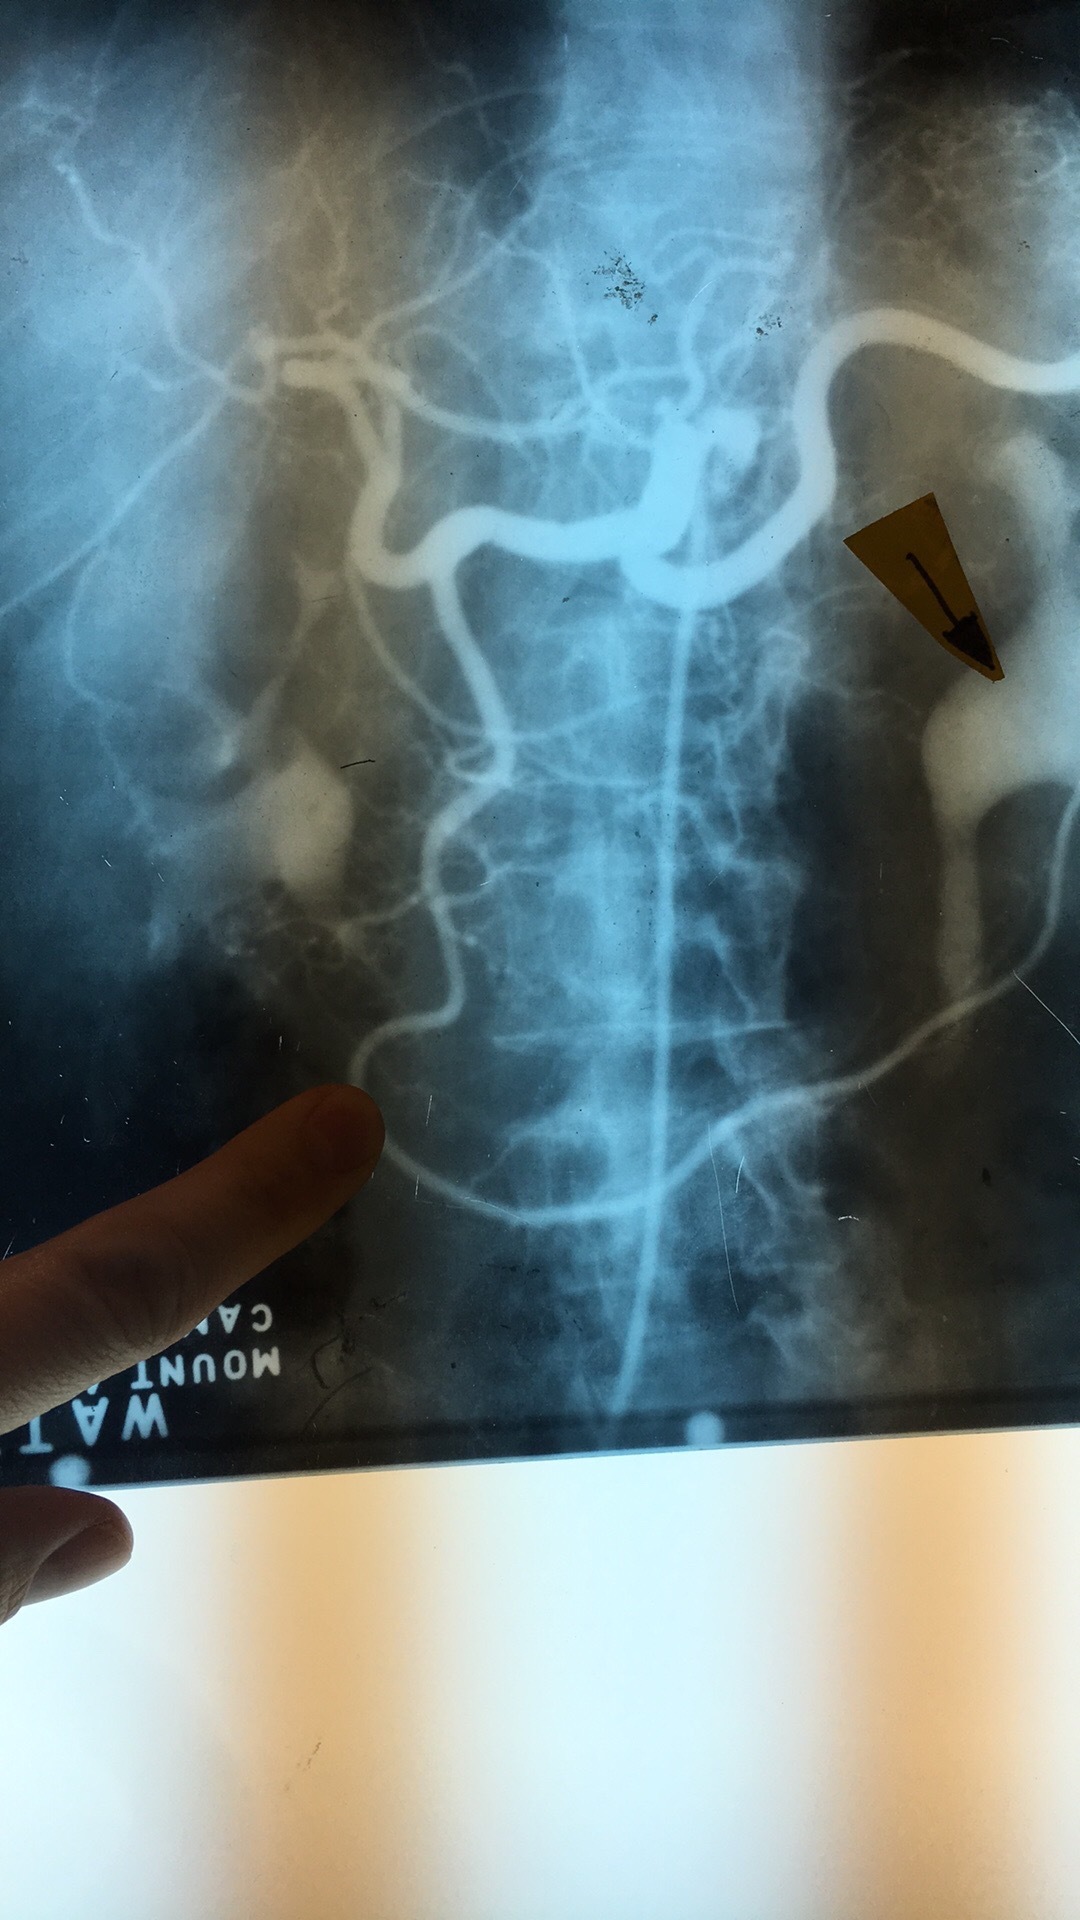

What artery? What comes off it?

Celiac Trunk. Left Gastric Art, Splenic Artery, Common Hepatic Artery